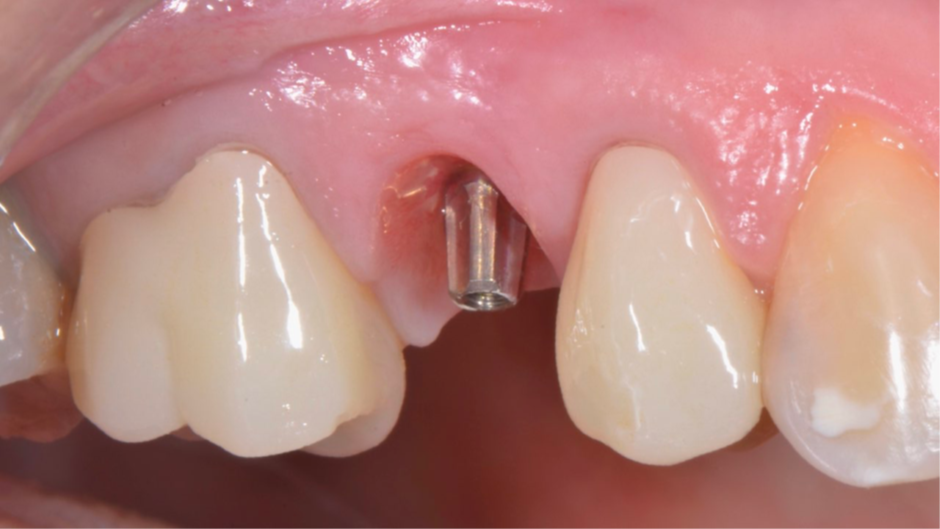

Após o planejamento virtual no programa Exoplan – Exocad (Figura 3) e confecçãode uma guia cirúrgica prototipada, foi realizada uma cirurgia guiada por computadorImplaguide 3.5/4.0 e instalado um implante Due Cone 3,5x9mm (Figura 4). Foi instalado também um cicatrizador de 3,5×2,5 (Figura 5). Após quatro meses de cicatrização, o implante estava com o cicatrizador aparente na mucosa (Figura 6).

Figura 4 – Instalação do implante Due Cone 3,5x9mm.

Figura 5 – Cicatrizador de 3,5×2,5 e RX de controle imediato.

Figura 6 – Pós-operatório de quatro meses.